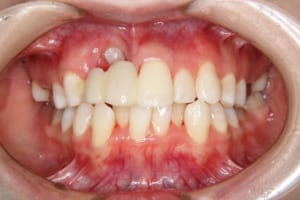

治療前

主訴 下の歯の凸凹

上の前歯が出ているのが気になる

その他/備考 上顎右側中切歯および側切歯が、埋伏していた犬歯によって歯根吸収していました。